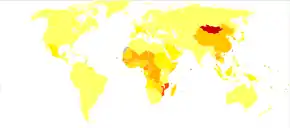

The vast majority of HCC cases and the lowest survival rates after treatment occur in Asia and sub-Saharan Africa, in countries where hepatitis B infection is endemic and many are infected from birth. The incidence of HCC in the United States and other developing countries is increasing due to an increase in hepatitis C virus infections. It is more than four times as common in males as in females, for unknown reasons.[4]

HCC is one of the most common tumors worldwide. The epidemiology of HCC exhibits two main patterns, one in North America and Western Europe and another in non-Western countries, such as those in sub-Saharan Africa, Central and Southeast Asia, and the Amazon basin. Males are affected more than females usually, and it is most common between the ages of 30 and 50.[83]

Hepatocellular carcinoma causes 662,000 deaths worldwide per year[84] about half of them in China.

Africa and Asia

In some parts of the world, such as sub-Saharan Africa and Southeast Asia, HCC is the most common cancer, generally affecting men more than women, and with an age of onset between the late teens and 30s.[16] This variability is in part due to the different patterns of hepatitis B and hepatitis C transmission in different populations – infection at or around birth predispose to earlier cancers than if people are infected later. The time between hepatitis B infection and development into HCC can be years, even decades, but from diagnosis of HCC to death, the average survival period is only 5.9 months according to one Chinese study during the 1970-80s, or 3 months (median survival time) in sub-Saharan Africa according to Manson's textbook of tropical diseases. HCC is one of the deadliest cancers in China, where chronic hepatitis B is found in 90% of cases. In Japan, chronic hepatitis C is associated with 90% of HCC cases. Foods infected with Aspergillus flavus (especially peanuts and corns stored during prolonged wet seasons) which produces aflatoxins pose another risk factor for HCC.

North America and Western Europe

The incidence of HCC is relatively lower in the Western Hemisphere than in Eastern Asia. However, despite the statistics being low, the diagnosis of HCC has increased since the 1980s and it is continuing to increase, making it one of the rising causes of death due to cancer. The common risk factor for HCC is hepatitis C, along with other health issues.[86][87]